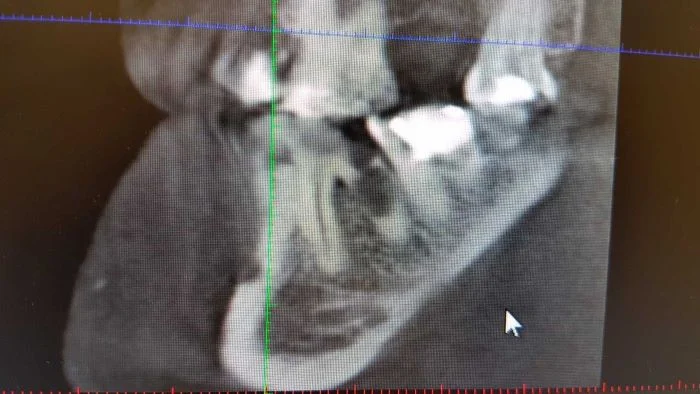

Read MoreИнтересный и сложный случай. Пациенту 36 лет. Наверху слева (или справа если от пациента) можно увидеть непрорезавшийся клык. Внизу слева - новообразование - остеома…